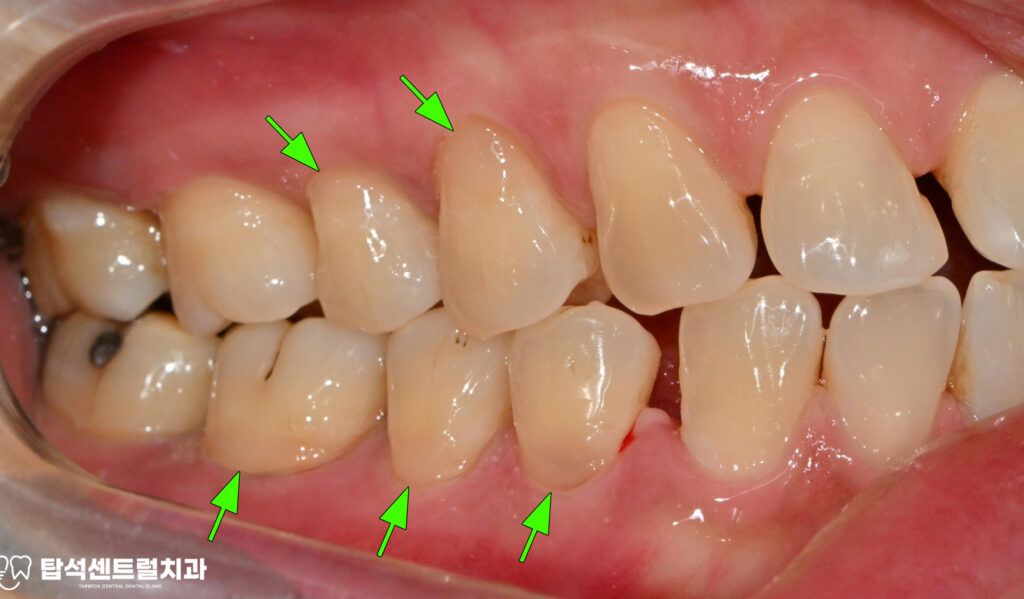

다수 치아에서 나타난 치경부 마모증은

레진으로 수복하는 것이 적절합니다.

치경부 마모증은 치아 목 부분이 닳아서

움푹 파인 상태를 말하며,잘못된 칫솔질이나

이갈이 습관으로 발생합니다.

치경부 마모증 부위도 레진으로 수복하여

전반적인 구강 환경을 개선했습니다.

레진 수복을 통해 자연 치아색과 유사한 재료로

자연스러운 외관을 유지할 수 있었습니다.